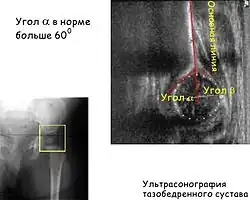

Ультразвуковая диагностика

Ультрасонография тазобедренных суставов детей первого года жизни является диагностическим стандартом[15].

Основным показанием к применению этого метода является факторы риска и клинические признаки дисплазии суставов у детей до 3 месяцев. Это достойная альтернатива рентгеновскому исследованию у детей до 6-месячного возраста. Ультразвуковой метод достаточно точен и практически безопасен для ребёнка.

При фронтальном срезе сонографическая картинка примерно соответствует изображению переднезадней рентгенограммы. В данном случае головка бедра центрирована, это норма. При исследовании можно определить смещение головки бедра при различных движениях. Если провести линию параллельно латеральной стенке подвздошной кости, то можно измерить так называемый угол α – угол наклона вертлужной впадины, который характеризует степень развития костной крыши. По мере созревания, этот угол увеличивается. Угол β характеризует степень развития хрящевой крыши. В зависимости от этих и многих других показателей суставы делятся на типы[16].

| Угол α * | > 60° | 50–59° | 43–49° | > 43° | 43° | |||||

| Угол β ** | < 55° | > 55° | 70–77° | > 77° | > 77° | |||||

- Угол α образован основной линией (проводится параллельно латеральной стенке подвздошной кости) и линией костной крыши, проводится от нижнего костного края подвздошной кости к верхнему костному краю вертлужной впадины.

Данный угол характеризует степень развития костной крыши.

- Угол β образован основной линией и линией хрящевой крыши, проводится от верхнего костного края вертлужной впадины через середину лимбуса.